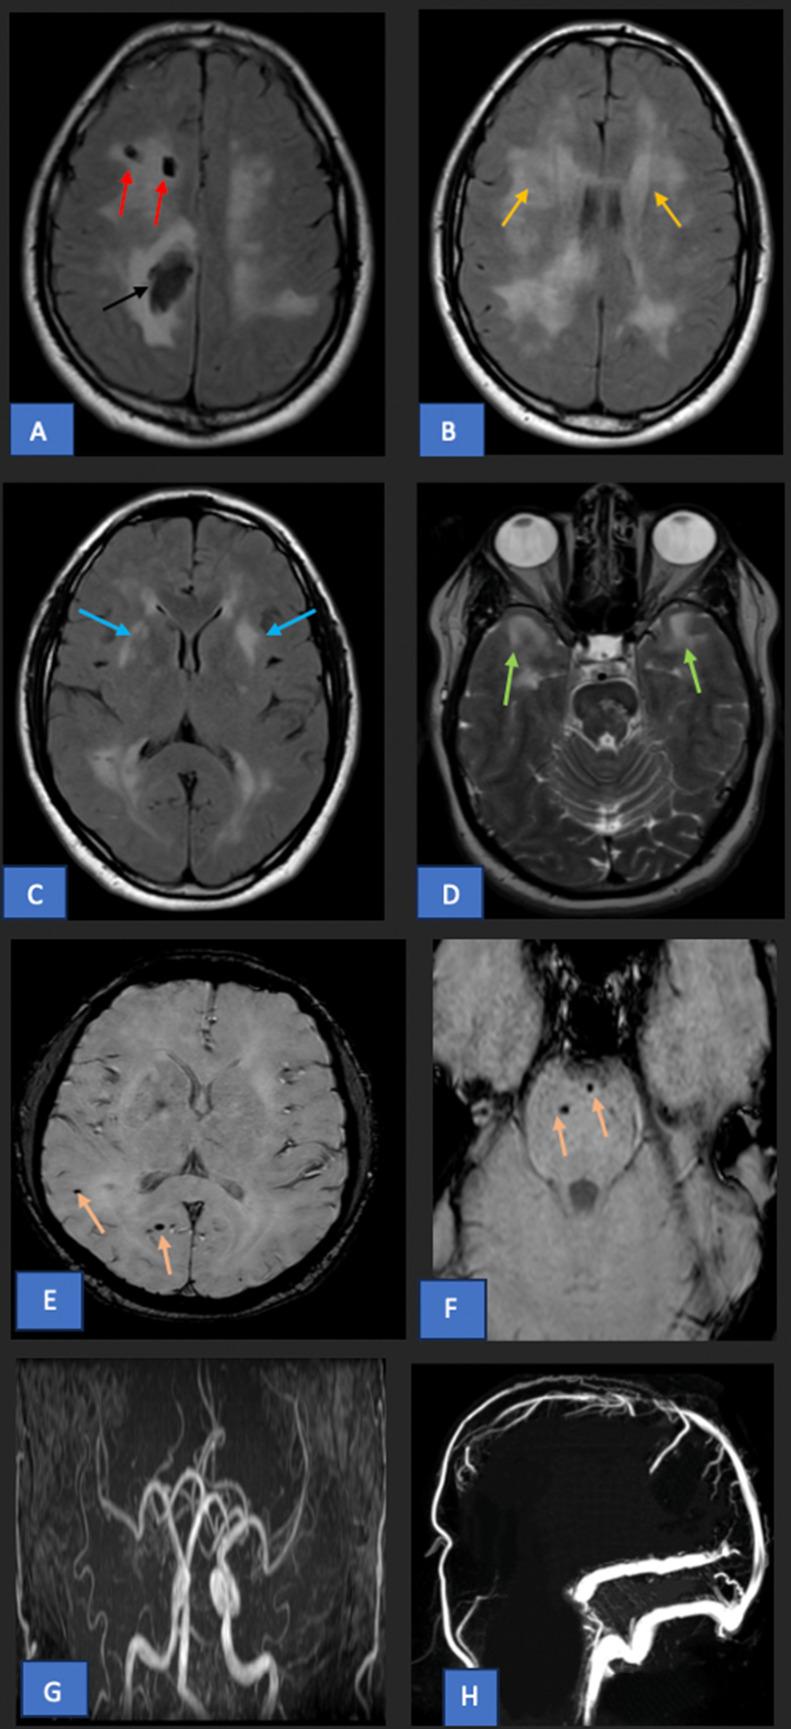

Cerebral autosomal dominant arteriopathy with subcortical infarcts and leukoencephalopathy (CADASIL) is a hereditary small vessel disease caused by mutations in the NOTCH3 gene. Its clinical presentation includes recurrent lacunar infarcts, transient ischemic attacks, cognitive decline, migraine, and psychiatric disorders. Neuroimaging typically reveals white matter changes, particularly in the basal ganglia, external capsules, and anterior temporal lobes. While CADASIL is primarily associated with ischemic events, hemorrhagic manifestations are rare. We present a case of a CADASIL patient who presented with left-sided hemiparesis. Imaging revealed a right paracentral intracerebral hemorrhage, an atypical finding in CADASIL. This case highlights the potential for hemorrhagic complications in CADASIL and emphasizes the importance of recognizing these rare presentations in clinical practice.

伴有皮质下梗死和白质脑病的常染色体显性遗传性脑动脉病(CADASIL)是一种由NOTCH3基因突变引起的遗传性小血管疾病。其临床表现包括反复发作的腔隙性梗死、短暂性脑缺血发作、认知功能下降、偏头痛和精神障碍。神经影像学检查通常显示白质改变,尤其是在基底节、外囊和颞叶前部。虽然CADASIL主要与缺血性事件相关,但出血性表现很少见。我们报告一例CADASIL患者,该患者表现为左侧偏瘫。影像学检查发现右侧脑中央旁脑出血,这在CADASIL中是一个非典型表现。该病例突出了CADASIL出血性并发症的可能性,并强调了在临床实践中认识这些罕见表现的重要性。